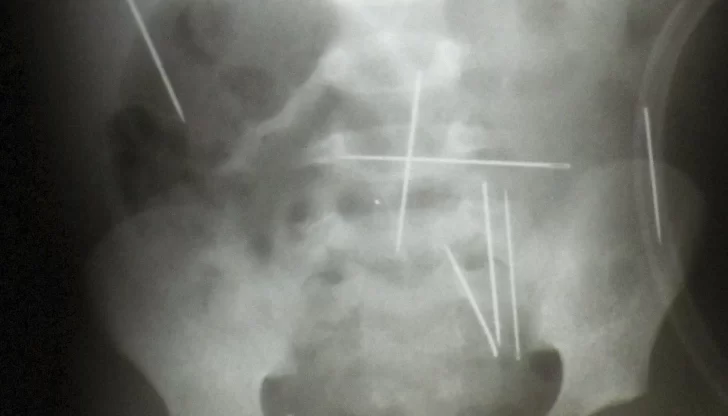

Un niño brasileño de dos años fue internado por tener 50 agujas en su cuerpo, dos de las cuales están alojadas en el corazón. La criatura fue sometida a un ritual de magia negra por su padrastro y deberá ser operado de urgencia.

"Descubrimos al menos dos agujas que están en el ventrículo izquierdo, en el corazón del niño", declaró a la televisión local Fabio Contelle, cirujano pediátrico del Hospital do Oeste de la ciudad de Barreiras, estado de Bahia (nordeste).

La extracción del resto de las agujas dependerá de futuras evaluaciones y del riesgo que presenten para su salud, precisó.

El resto de la agujas se encuentran alojadas en su tórax, abdomen, cuello y piernas. El niño se encuentra grave pero estable, está conciente, respira normalmente y es alimentado por sonda.